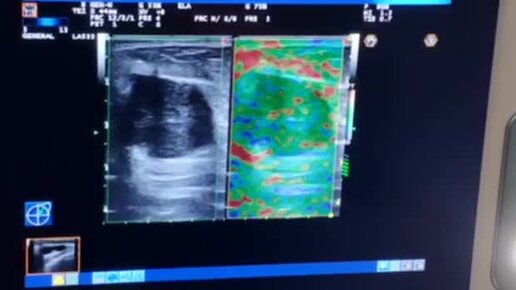

Метастазы рака

Маммология и хирургия РНЦРР